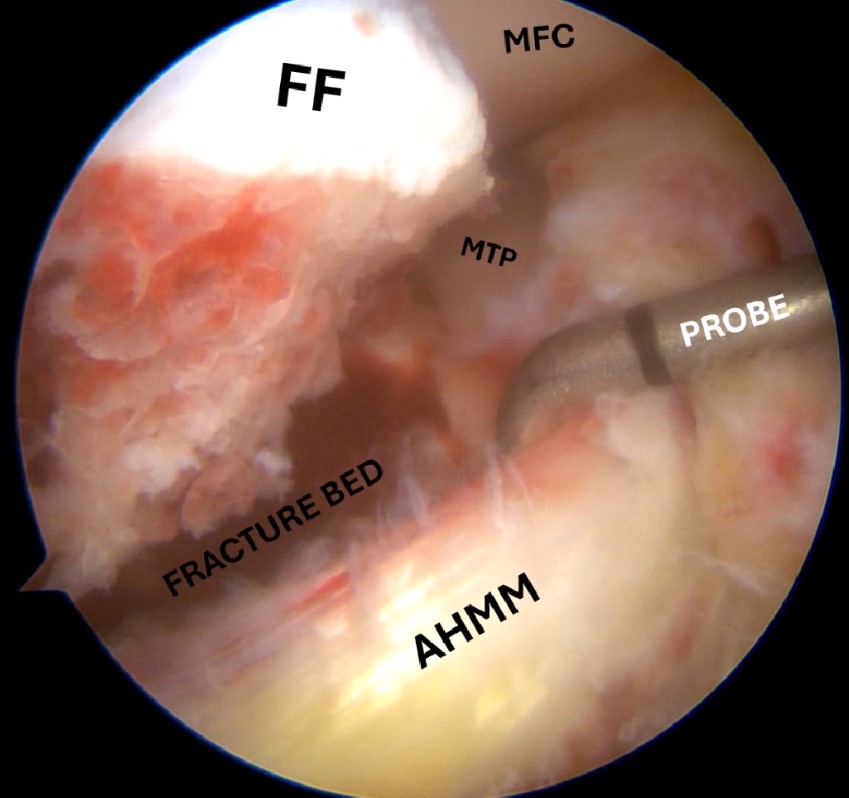

Figure 7. Arthroscopic view of medial meniscus entrapment in the fracture side; the anterior horn of the medial meniscus is retracted with the probe in order to disengage the fracture fragment.

FF, fracture fragment; MTP, medial tibial plateau; AHMM, anterior horn of the medial meniscus.